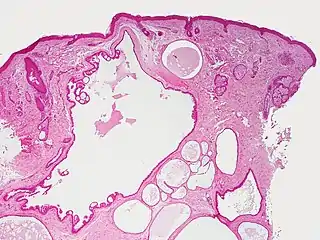

Hidrocistoma

El hidrocistoma (también conocido como cistoadenoma,[1] quiste de las glándulas de Moll,[1] o quiste sudorífero[1]) es un adenoma de las glándulas sudoríparas.[2] : 787

Los hidrocistomas son quistes de los conductos del sudor, generalmente en los párpados.[3] : 664 No son tumores.

Generalmente surgen de las glándulas apocrinas. También se les llaman quistes de Moll o quistes sudoríferos. Puede haber un tipo de hidroadenoma que surge de las glándulas ecrinas, pero estos son poco comunes.